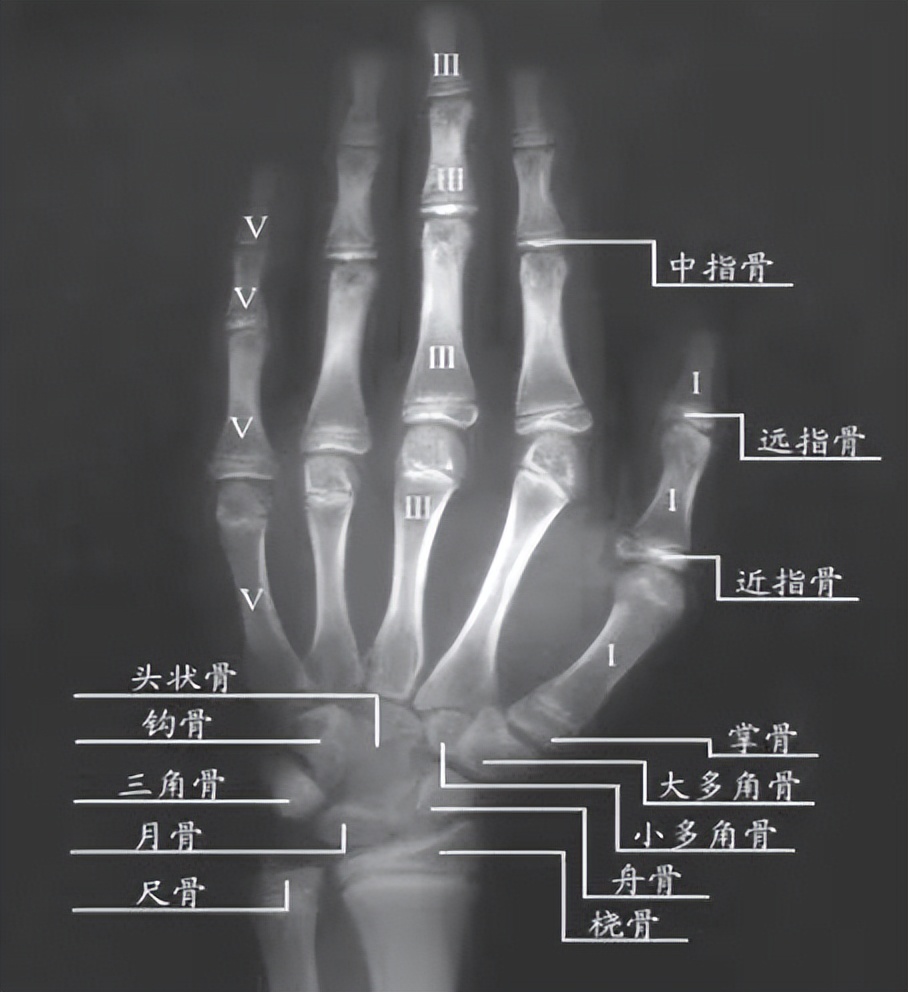

通常拍摄左手手腕部位的X光片,通过X光片观察左手掌指骨、腕骨及桡尺骨下端的骨化中心的发育程度来确定骨龄。